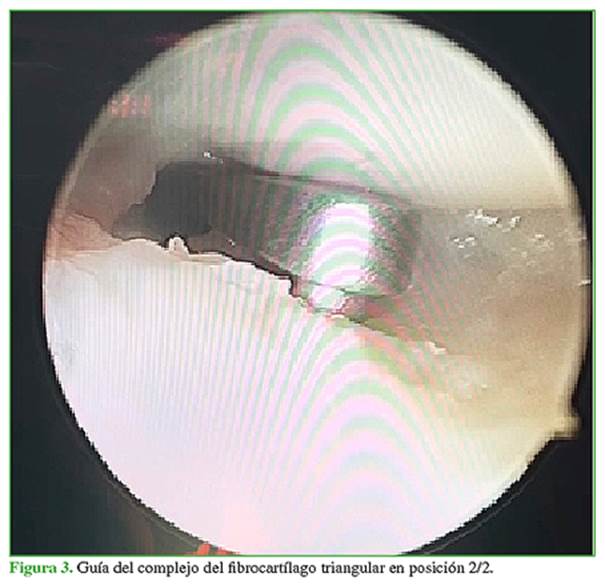

Se procede a la sinovectomía y el desbridamiento de la lesión (Figura 2). A continuación, se coloca la guía del CFCT por el portal 6R y bajo visión ¾, se coloca la guía en la zona 2/2 descrita por Matsumoto (Figura 3). Se efectúa un abordaje cubital de 2 cm para colocar la guía al mismo tiempo que se la posiciona por el portal 6R y se coloca una clavija por la guía hasta salir en la articulación y asegurarse de estar en la zona 2/2. Se fresa con una guía de 3.0 desde el cúbito hasta la articulación. Al finalizar se retira la guía y se coloca por el orificio cubital un pasador de hilo 2.0 tipo fiberwire penetrando el disco; se retira ese hilo por el portal 6R sin perderlo por el túnel cubital (Figuras 4-6). A continuación, se coloca un pasador de hilo con un rescatador de sutura por el túnel cubital penetrando el disco 2 mm a volar o dorsal y se retira el rescatador de sutura por el portal 6R (Figuras 7-9). Se pasa el hilo por el rescatador de sutura y se tira desde el rescatador de sutura por el abordaje cubital siempre mirando desde portal ¾. Se observa cómo la sutura pasa hacia el orificio cubital tensando el fibrocartílago (Figuras 10-12). Mediante un dispositivo de anclaje sin nudo de 2,8 mm se colocan las dos puntas de los hilos dentro del sistema de fijación y se lo impacta 5 mm distal al túnel realizado (Figuras 13 y 14). Se comprueba que las pruebas del trampolín y del gancho sean negativas, se retira la tracción y se prueba la estabilidad. Se cierran los portales. Se coloca una férula tipo Munster (pinza de azúcar) por cuatro semanas con movilidad de dedos y hombro, y luego, se inicia el programa de rehabilitación. Las primeras dos semanas se realiza con férula corta ballenada de muñeca de uso permanente, solo se retira la férula en rehabilitación y dentro de la casa para una movilidad controlada de la muñeca. Luego de las seis semanas, se usa la férula rígida de muñeca por la noche únicamente y se indica la movilidad enérgica de la muñeca libre sin carga. A las ocho semanas, se comienza con la fuerza progresiva y se retira, en forma definitiva, la muñequera.